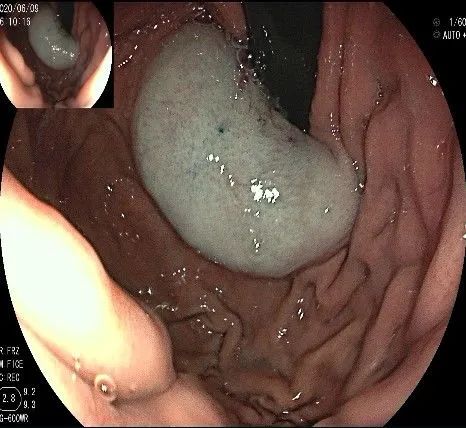

倒镜观察,可见贲门部一个明显的隆起,中央部分的凹陷,是4天前取活检留下的。

我们的思路:病变长径约2.0cm,位置活动,倒镜后先在胃底侧粘膜下注射,使病变向食管腔方向抬举,然后再在食管腔内做粘膜下注射切开,以获得一个好的术野,果然,注射后粘膜抬举明显,瘤体被挤向口侧。

正镜观察,瘤体就在贲门部齿状线的下方。